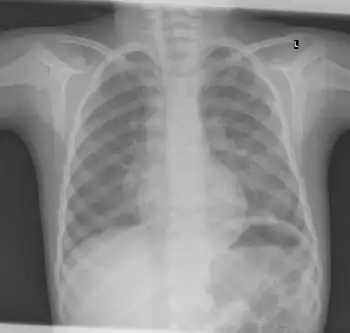

X-ray ribs: multiple enchondroma -